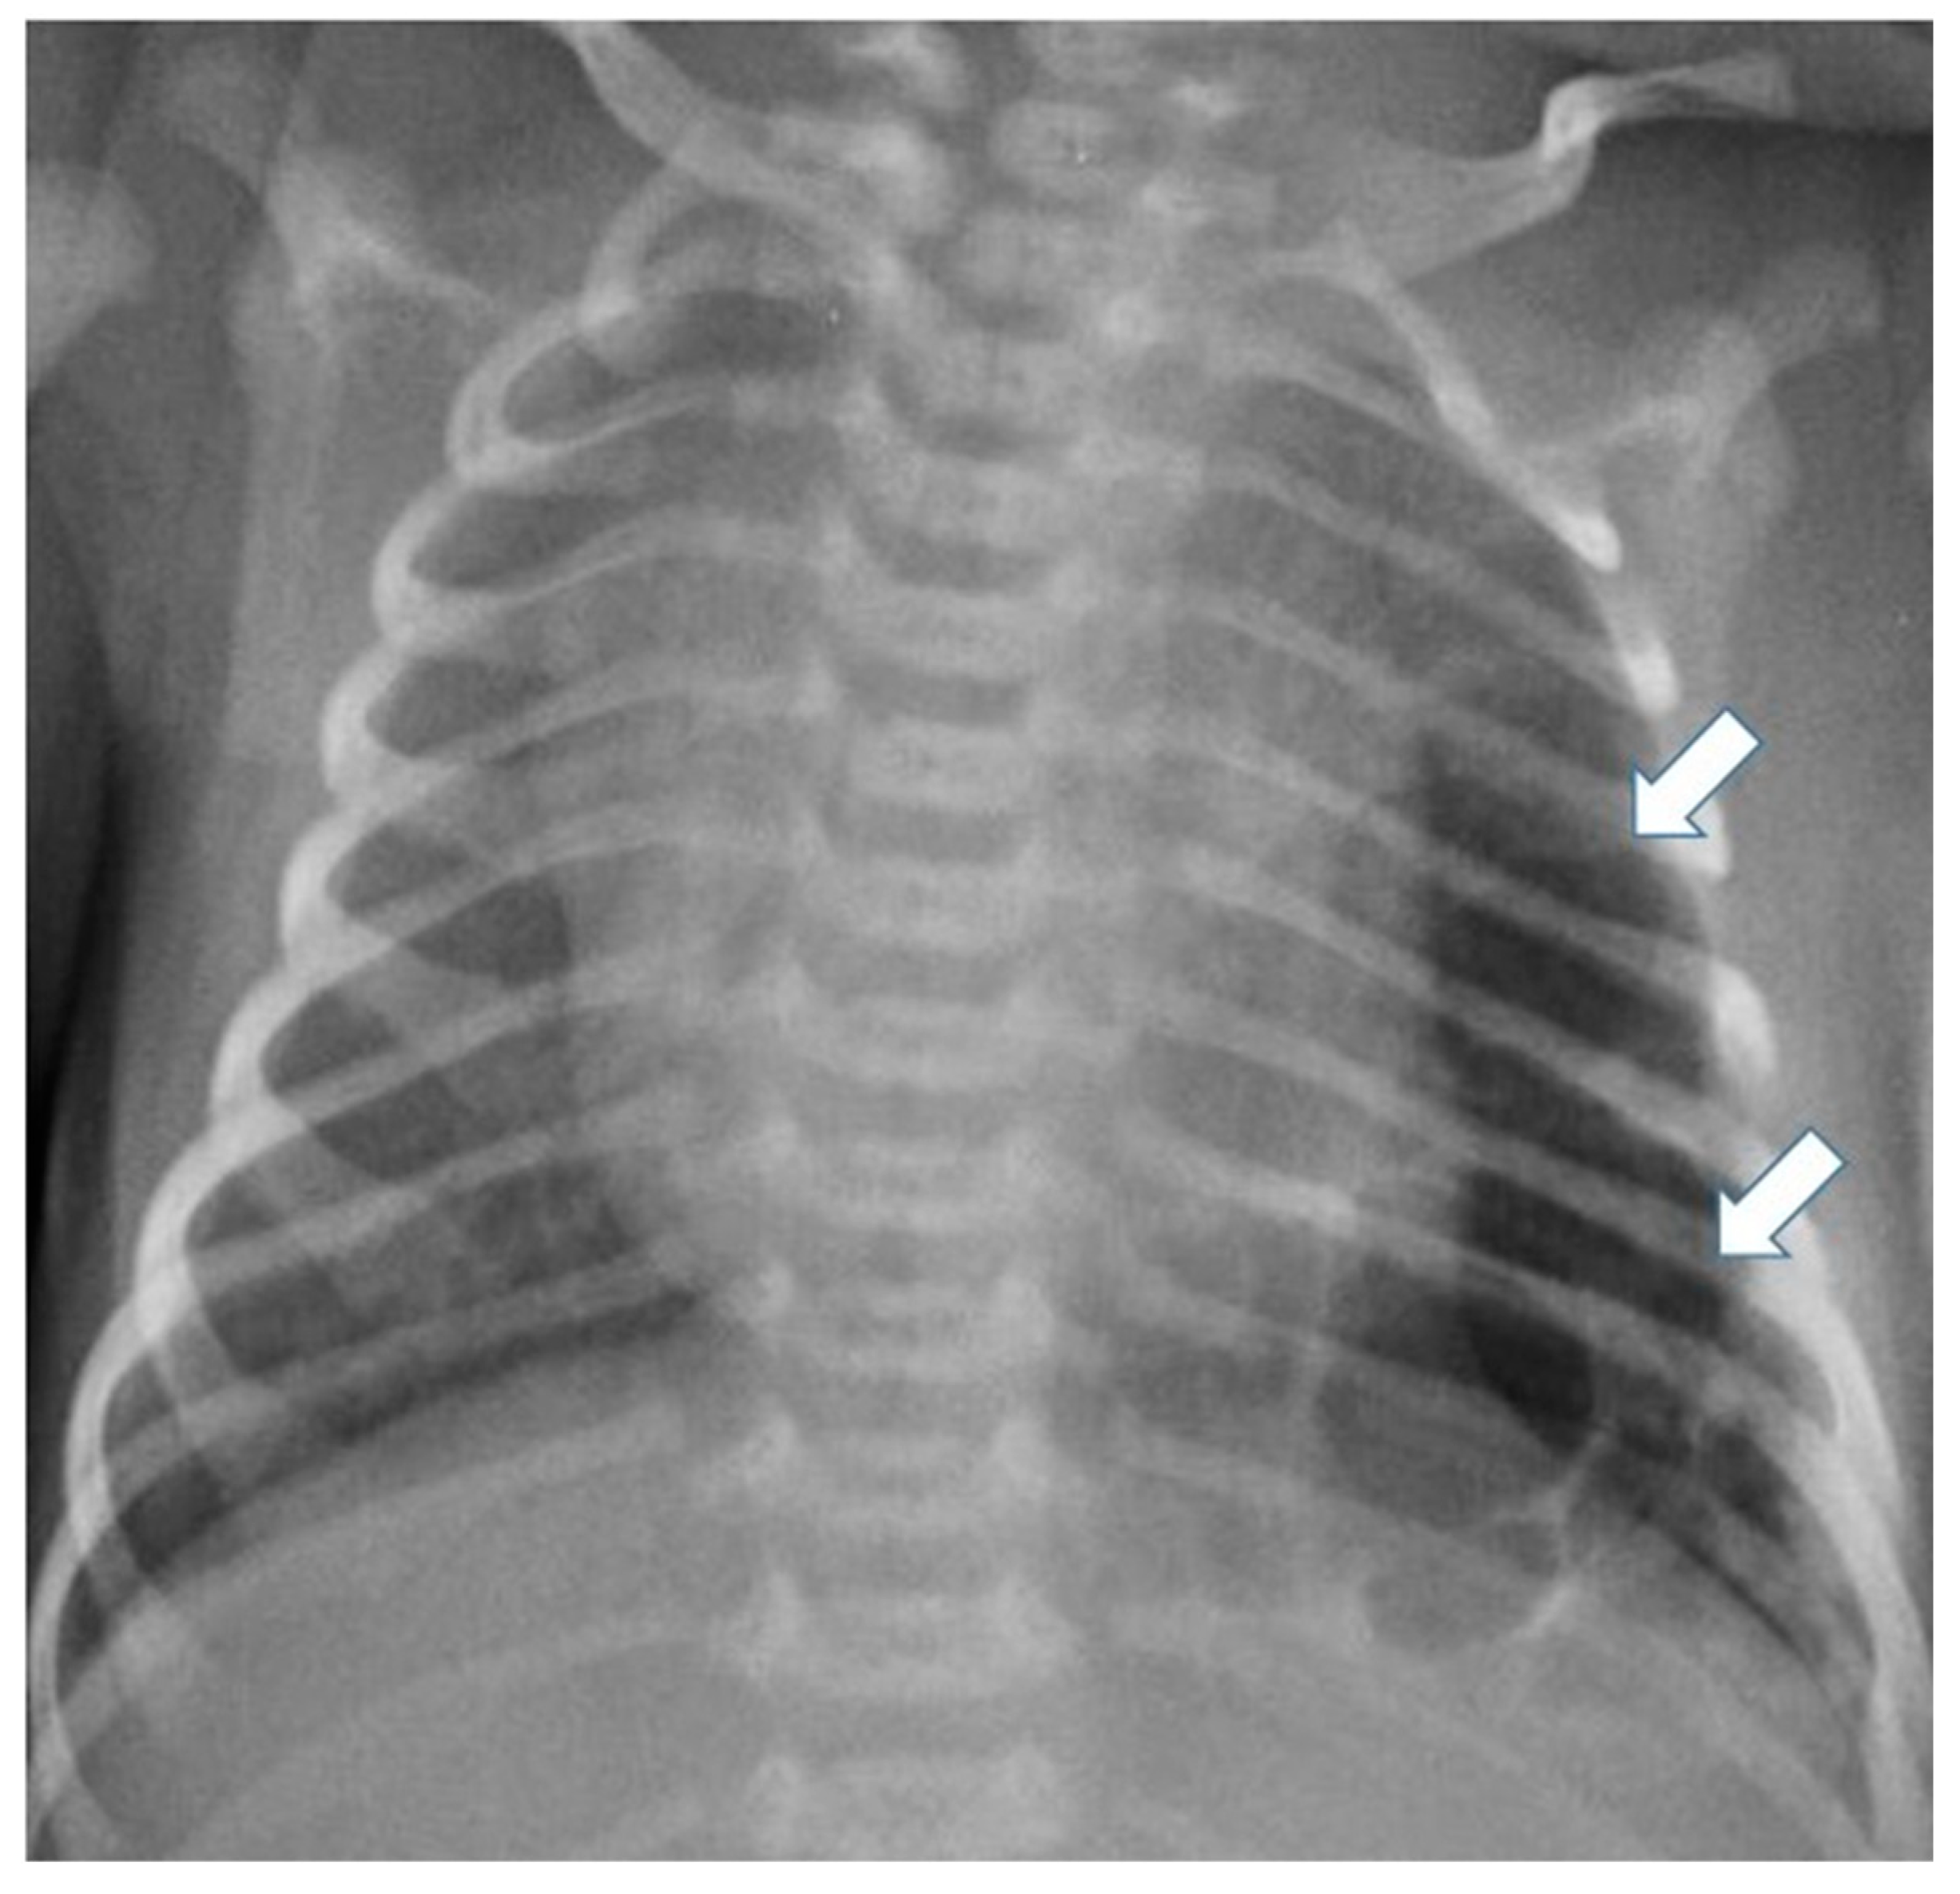

3.4.2. Congenital Pulmonary Airway Malformations

3.4.3. Congenital Lobar Hyperinflation

3.4.4. Congenital Bronchial Atresia

3.4.5. Bronchogenic Cysts